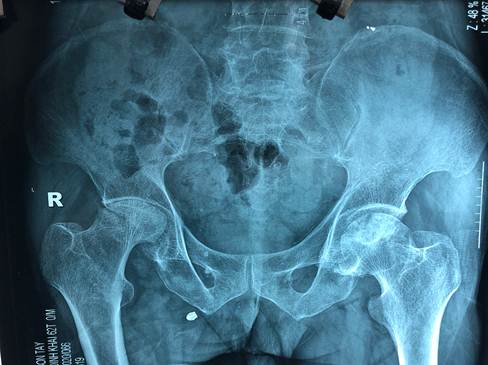

Người bệnh có tiền sử tiểu đường , tăng huyết áp đã điều trị nhiều năm. Hiện tại có hoại tử vô khuẩn, thoái hoá dính khớp háng 2 bên, đau và hạn chế đi lại nhiều, ảnh hưởng cuộc sống sinh hoạt hàng ngày.

Người bệnh được làm các xét nghiệm cơ bản, chụp CT scaner khớp háng 2 bên, khám toàn diện. Bệnh viện đã tiến hành phẫu thuật thay khớp háng Ceramic toàn phần không xi măng bên phải cho người bệnh.